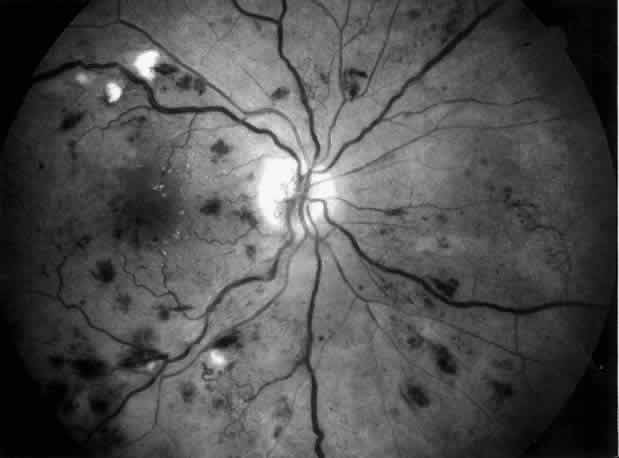

Arterial hypertension is a frequent complication of congenital and acquired renal and renovascular disorders. Arteriolar narrowing, tortuosity, and arteriovenous nicking are common retinal vascular abnormalities in patients with arterial hypertension. In subjects with malignant hypertension, ischemic changes may occur in retina, choroid, and optic nerve and produce cotton-wool spots, flame-shaped hemorrhages, hard exudates, Elschnig's spots, exudative detachment, papilledema, and optic atrophy (Fig. 1). In patients with severe and long-standing hypertension a sudden relative fall in arterial pressure may cause infarction of the optic nerve and blindness. Anterior ischemic optic neuropathy and retinal infarction have been described as complications of hemodialysis-associated hypotension. Uremia, anemia, and papilledema of intracranial hypertension are other risk factors for optic neuropathy in patients with chronic renal diseases.2 In addition, patients with chronic hypertension are predisposed to retinal arterial and venous obstructive diseases leading to visual loss.

Fig. 1. Malignant hypertension with retinal and choroidal vascular manifestations: retinal hemorrhages, exudative retinal detachment, numerous edematous Elschnig's spots (A), and fluorescein angiographic abnormalities with areas of hypoperfusion of the choriocapillaris in the early phase (B), and diffuse leak of fluorescein in the late phase of angiography (C).